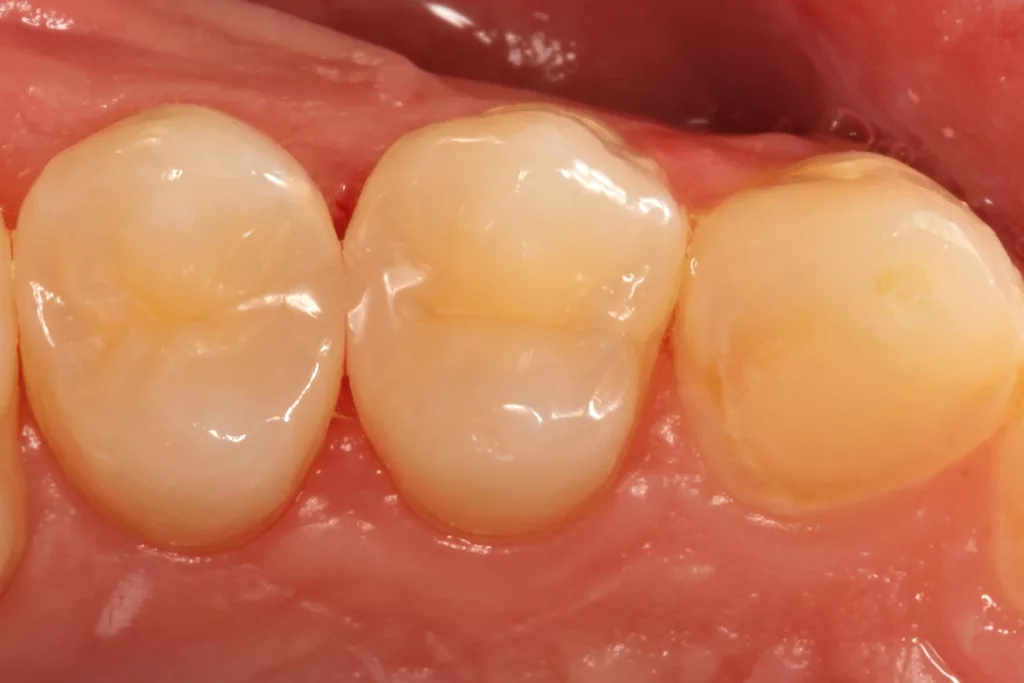

Fall 5: Versorgung einer okklusalen Kavität an einem unteren Molaren

Auch im Molarenbereich können Bulkflow-Materialien effektiv und ökonomisch eingesetzt werden, ohne Abstriche an der Ästhetik machen zu müssen, was der Fall des hier versorgten Zahnes 46 bei einer 22-jährigen Patientin zeigt. Die Abbildung 24 stellt die bereits präparierte und mit einem Einzelzahnkofferdam isolierte Kavität mit der Phosphorsäurekonditionierung der Schmelzränder (Gel Etchant, Kerr) dar. Die Entscheidung zur absoluten Trockenlegung fiel aufgrund der nicht so einfach kontrollierbaren Zunge und der vielen Schluckreflexe, was das Risiko einer ungewollten Speichelkontamination der Klebefläche unverhältnismäßig erhöhte.

Die Verwendung des Kofferdams ist generell eine sehr empfehlenswerte, aber keine zwingende Voraussetzung zur Etablierung einer suffizienten Kontaminationskontrolle [47,96]. Das bisher auch bereits verwendete Zwei-Schritt-Universaladhäsiv G2 Universal wurde hier in der selektiven Schmelzätztechnik angewendet, d.h., das Material arbeitet auf dem Dentin selbstkonditionierend (Abb. 25). Die bislang zu diesem innovativen Mehrflaschen-Universaladhäsiv publizierten Daten zeigen eine beeindruckende Performance, die den Vergleich mit sogenannten Goldstandards [98] wie einem Optibond FL nicht scheuen müssen [13,18,34,58,63,114,119,127,130]. Im nächsten Schritt wurden die einzelnen Höcker mit dem angenehm standfesten Flowable aufgebaut (Abb. 26). Die Abbildung 27 zeigt die komplett versorgte okklusale Kavität, die Abbildung 28 die Situation unmittelbar nach Ausarbeitung und Politur. Erneut beeindruckt die gute Farbadaptation.